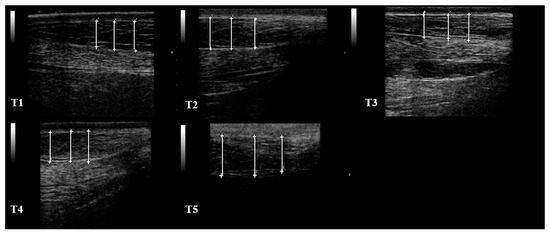

2.4. RTU Assessment of SF Thickness